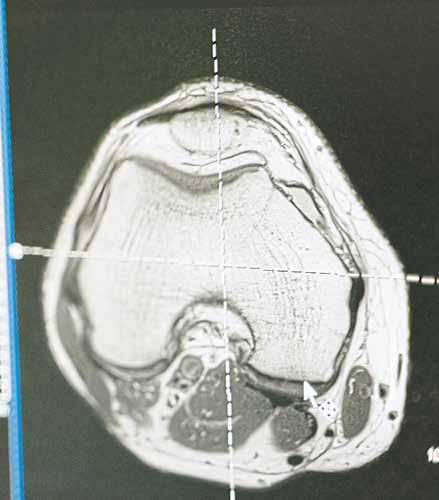

Bei der Krebstherapie spielen Bilder eine ganz zentrale Rolle. Bei schwierigen Operationen ist sehr wichtig, den Tumor anhand von Bildern auf der Basis von dreidimensionalen CT- oder MRT-Datensätzen genau vom gesunden Gewebe abzugrenzen. Bei dieser in der Praxis zeitintensiven Arbeit schafft KI

inzwischen Ergebnisse, die mit denen von Experten vergleichbar gut sind. Ebenso können diese Informationen während der Operation zur Navigation genutzt werden. Das gleiche gilt für die Strahlentherapie, denn es ist wichtig, möglichst nur den Tumor zu bestrahlen und das darum herumliegende Gewebe zu schonen.

Die KI wird mit zahlreichen Bildern von Tumoren trainiert und analysiert sie. Durch dieses Deep-Learning-Verfahren lernt das System immer besser, selbständig Bilder auszuwerten.